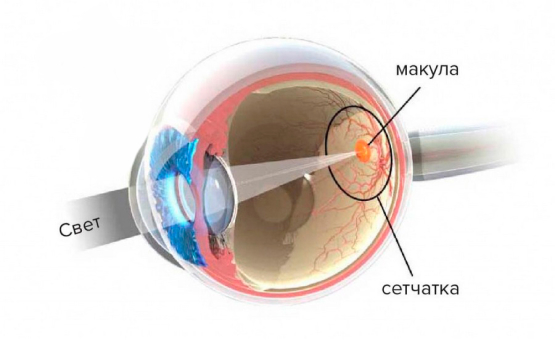

Изображения и анатомия сетчатки глаза